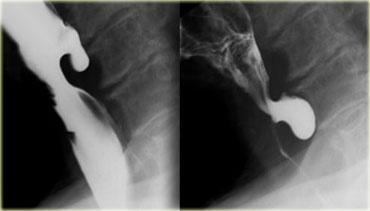

Bên trái là hình ảnh nam bệnh nhân 52 tuổi với triệu chứng nuốt khó từng đợt.

Hình ảnh ngoài cùng bên trái không cho thấy bất thường, tuy nhiên thực quản đoạn xa chưa giãn căng.

Khi thực quản đoạn xa giãn căng, vòng B Schatzki rộng 13 mm (các mũi tên) gây tắc nghẽn từng đợt được hiển thị rõ tại đỉnh của thoát vị hoành (đầu mũi tên).

Bên trái là hình ảnh nam bệnh nhân 71 tuổi với triệu chứng đau ngực sau bữa ăn nhanh.

Khiếm khuyết ngấm thuốc gây tắc nghẽn ở đoạn xa (mũi tên) là một mảnh thịt đã di chuyển vào dạ dày trong quá trình thăm khám.

Hình ảnh thực quản chụp theo dõi cho thấy vòng B Schatzki (các mũi tên) là nguyên nhân gây tắc nghẽn.